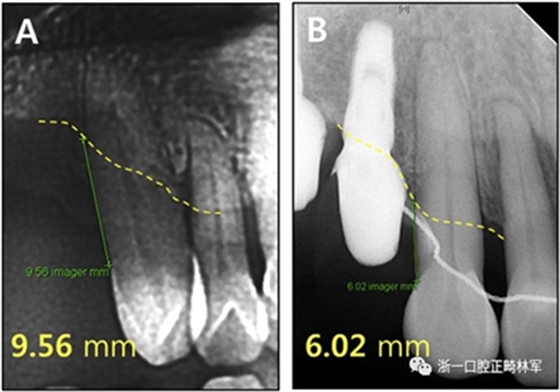

我們的患者,在治療之前,上頜右側尖牙近中傾斜并且萌出過度。盡管后牙區(qū)沒有用于支抗的牙齒,但通過合理地使用TADs的力學作用,尖牙以改善的角度被推入。

根據(jù)治療前后的根尖X光片,可以發(fā)現(xiàn)存在3.5mm顯著改善的放射線骨水平(圖15),并且臨床上牙周袋深度減少(表IV)。此外,力的推入性成分在向遠中移動期間誘導了上頜切牙的推入,并且在根尖X線照片上看到牙槽骨水平的改善。

圖15.上頜右側尖牙放射性骨水平:A,治療前;B,治療后